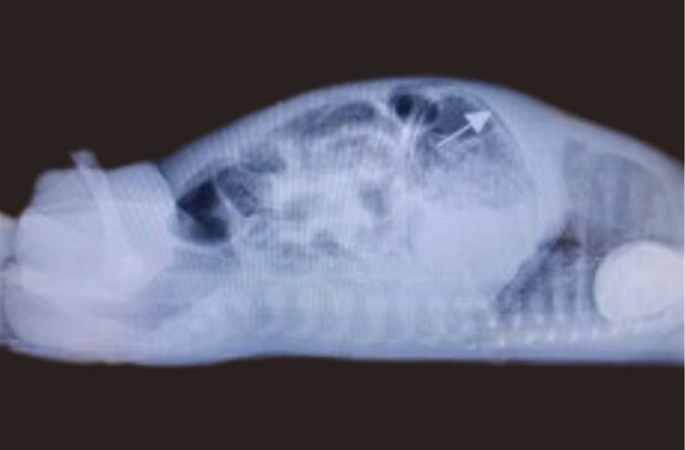

Bowel wall was notably thickened with air in the rectum. As gastric pneumatosis was a finding new to the managing team, intestinal perforation was initially considered; therefore a cross table lateral was requested, which confirmed gastric pneumatosis and pneumoperitoneum was ruled out, see Figure 2.Thrombocytopenia was noted. The lowest count observed was 70x103/uL (x109/L). Radiological and clinical findings therefore were in keeping with NEC stage 2a. He was re-screened and placed on Amoxicillin/Clavulanate potassium and Ceftazidime (second line as per local protocol) and Metronidazole was added.

Figure 2.Cross table lateral radiograph showing gastric pneumatosis (arrow shown)